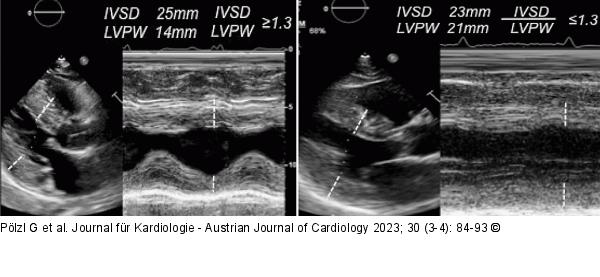

Abbildung 2: Hypertrophe Kardiomyopathie - Kardiale Amyloidose Verteilung der linksventrikulären Hypertrophie. Links: Hypertrophe Kardiomyopathie mit asymmetrischer linksventrikulärer Hypertrophie. Rechts: Kardiale Amyloidose mit symmetrischer linksventrikulärer Hypertropie. |